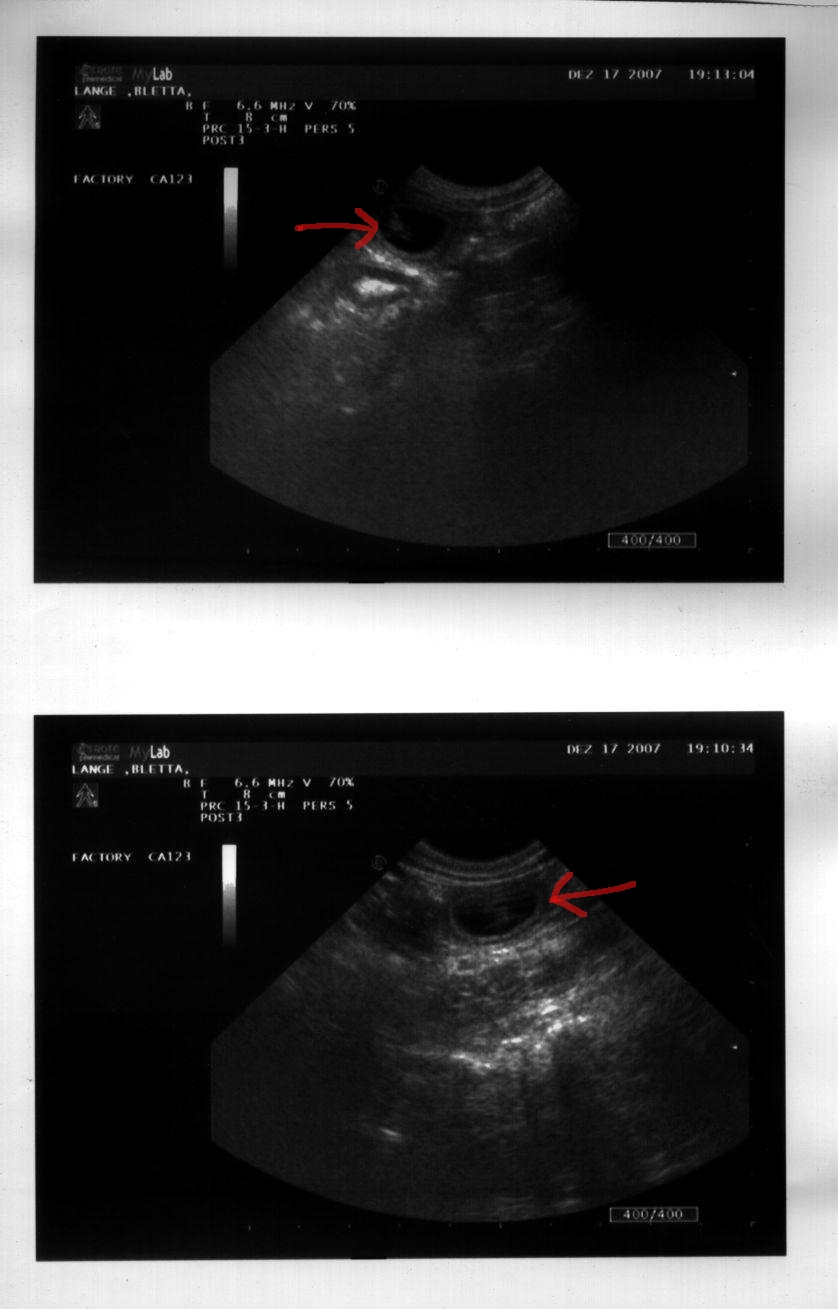

17.12.2007

Die ersten drei Wochen seit Blettas Rendez-Vous mit Touffie sind um, und wir haben einen Termin beim Tierarzt. Die Spannung ist groß - war der Besuch in Heiligenhaus erfolgreich?

Und tatsächlich sehen wir auf dem Ultraschall deutlich mehrere Welpen - Bletta ist trächtig!

Jetzt beginnt die Zeit, zu der sich die Welpen in der Gebärmutter einnisten und ihre Organe ausbilden. Bletta läßt sich noch nichts weiter anmerken, aber wenn sie auf dem Rücken liegt, ist ihr Bauch schon nicht mehr so flach wie vorher. Wir sind sehr zuversichtlich, daß dieses Mal alles gut gehen wird.

Das Ultraschallbild vom 17.12.2007